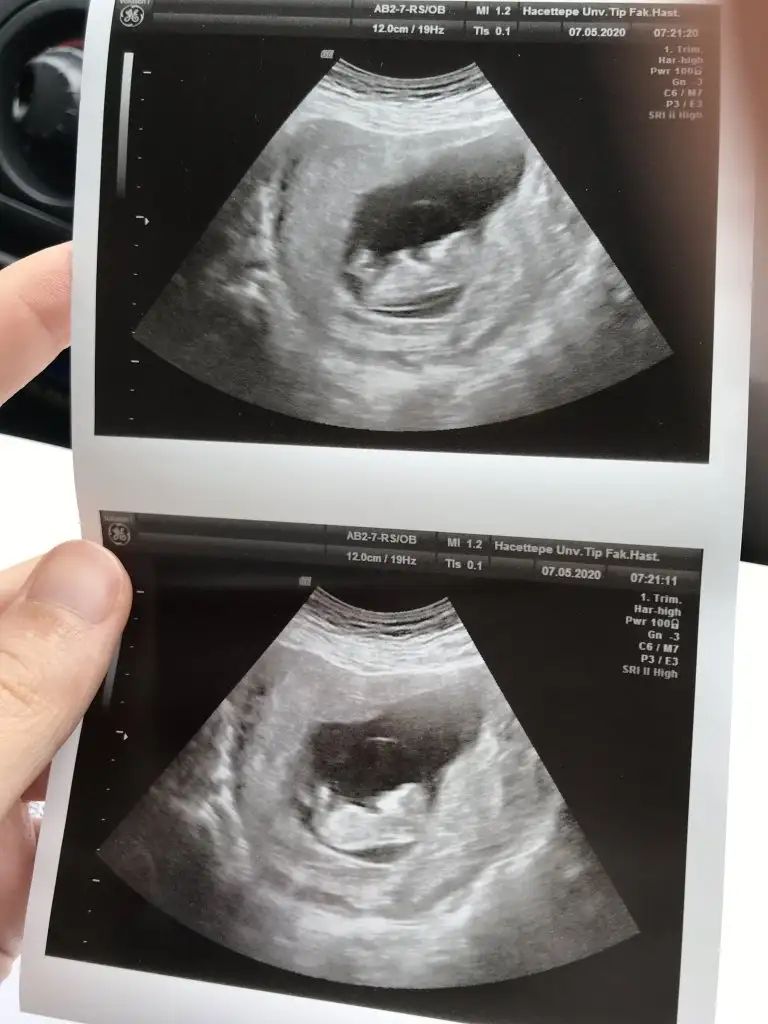

Yaa birisi hiç görünmüyor ya benim de biri net ama diğeri yok Orta da kesesi de net görünmüyor ileriki haftalarda gösterir inşallah bakalım

Ben tek bebek sandım benimkinin kesesi ile çok benzer belli olanın benim de yarın kontrol var bakalım sağlıkla devam ediyordur inşallah tahmin yaparsa Dr haberdar ederim

Eklentiler

• IMG_20200507_123241.webp

32,2 KB · Görüntüleme: 66

Eki Görüntüle 2631340 Kızlar bizde geldik kontrolden eli ayağı durmuyordu MaşaAllah o yüzden nubu pek görünmedi 1 hafta sonra tekrar gideceğim. Sat 10+0 ama 11+1 çıktı ilerdeymişiz:)

Yaaa Maşallah bunun kolları bacakları belli olmuş yaaa çok heyecan yaptım şimdi sabırsızlıkla pazartesi gelsin Masalllah canım çok güzel